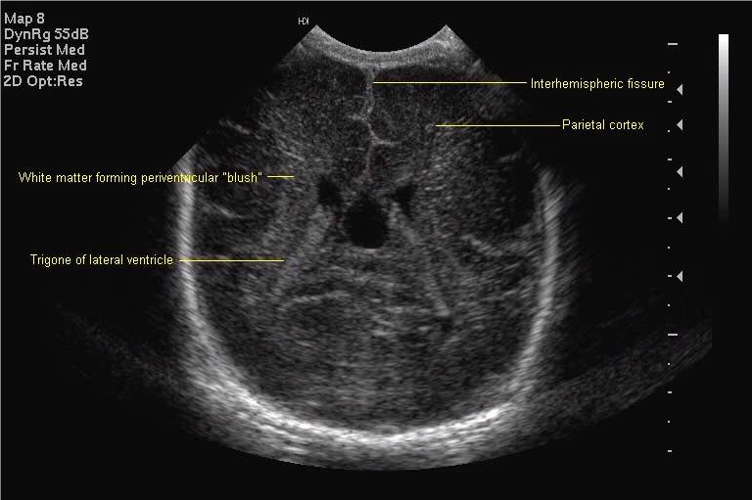

Standard views for cranial ultrasonography of the newborn

Posterior coronal